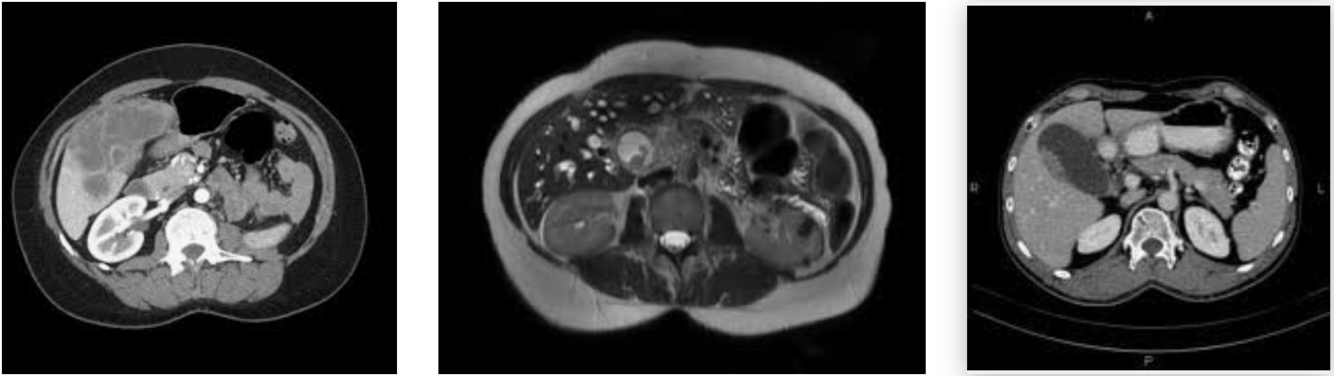

Biliary neoplasia: GB mets

Dx?